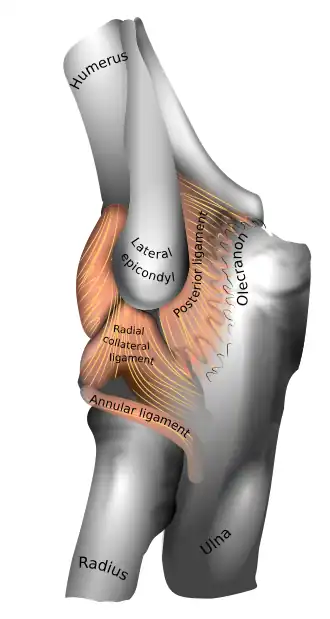

Left elbow-joint

Left: anterior and ulnar collateral ligaments

Right: posterior and radial collateral ligaments

The elbow, like other joints, has ligaments on either side. These are triangular bands which blend with the joint capsule. They are positioned so that they always lie across the transverse joint axis and are, therefore, always relatively tense and impose strict limitations on abduction, adduction, and axial rotation at the elbow.[8]

The ulnar collateral ligament has its apex on the medial epicondyle. Its anterior band stretches from the anterior side of the medial epicondyle to the medial edge of the coronoid process, while the posterior band stretches from posterior side of the medial epicondyle to the medial side of the olecranon. These two bands are separated by a thinner intermediate part and their distal attachments are united by a transverse band below which the synovial membrane protrudes during joint movements. The anterior band is closely associated with the tendon of the superficial flexor muscles of the forearm, even being the origin of flexor digitorum superficialis. The ulnar nerve crosses the intermediate part as it enters the forearm.[8]

The radial collateral ligament is attached to the lateral epicondyle below the common extensor tendon. Less distinct than the ulnar collateral ligament, this ligament blends with the annular ligament of the radius and its margins are attached near the radial notch of the ulna.[8]